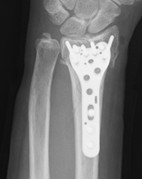

【骨折型に応じた各種プレート固定】

写真2

写真3

写真2:関節面の粉砕骨折に対する関節面固定に重点をおいたプレート固定

写真3:関節面、さらには長い骨折線をもつ骨折に対する長めのプレート固定